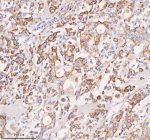

Immunohistochemical staining of SLC14A1 using anti-SLC14A1 antibody. SLC14A1 was detected in a paraffin-embedded section of human melanoma tissue. Heat mediated antigen retrieval was performed in EDTA buffer (pH 8.0, epitope retrieval solution). The tissue section was blocked with 10% goat serum. The tissue section was then incubated with 2 ug/ml rabbit anti-SLC14A1 antibody overnight at 4oC. Peroxidase Conjugated Goat Anti-rabbit IgG was used as secondary antibody and incubated for 30 minutes at 37oC. The tissue section was developed using an HRP secondary and DAB substrate.